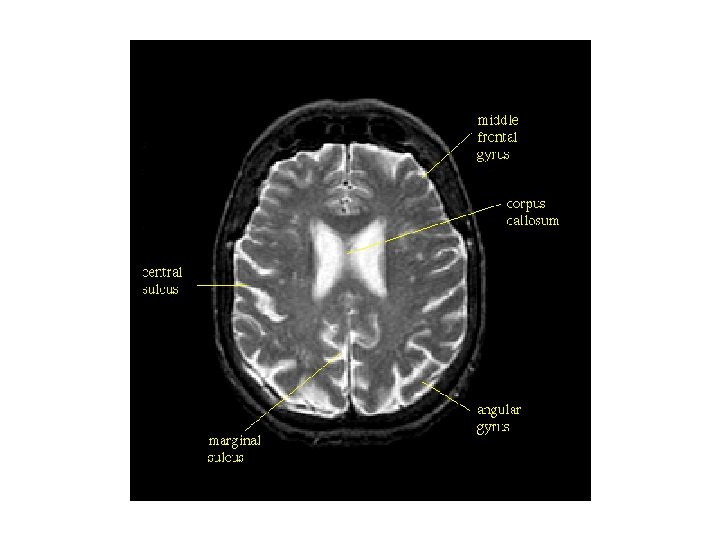

대뇌 외측표면에서 관찰되는 구조 1. 외측고랑(lateral fissure) 3. 하전두이랑 안와부(pars orbitalis) 5. 하전두이랑 삼각부(pars triangularis) 7. 하전두이랑 판개부(pars opercularis) 9. 상전두이랑(superior frontal gyrus, 상전두회) 11. 상전두고랑(superior frontal sulcus, 상전두구) 13. 중심전이랑(precentral gyrus, 전중심회) 15. 중심후이랑(postcentral gyrus, 후중심회) 17. 두정엽내고랑(intraparietal sulcus) 19. 변연상이랑(supramarginal gyrus, 연상회) 21. 두정후두고랑(parieto-occipital sulcus) 23. 외측후두이랑(lateral occipital gyrus) 25. 외측고랑 뒷가지(posterior ramus, 후지) 27. 하측두이랑(inferior temporal gyrus) 29. 상측두고랑(superior temporal sulcus) 31. 측두극(temporal pole) 2. 전두극(frontal pole) 4. 외측고랑 앞가지(anterior ramus, 전지) 6. 외측고랑 오름가지(ascending ramus, 상행지) 8. 하전두고랑(inferior frontal gyrus, 하전두구) 10. 중간전두이랑(middle frontal gyrus, 중전두회) 12. 중심전고랑(precentral sulcus, 전중심구) 14. 중심고랑(central sulcus, 중심구) 16. 중심후고랑(postcentral sulcus, 중심후구) 18. 상두정소엽(superior parietal lobule) 20. 각이랑(angular gyrus, 각회) 22. 후두극(occipital pole) 24. 후두전패임(preoccipital notch) 26. 하측두고랑(inferior temporal sulcus) 28. 중간측두이랑(middle temporal gyrus) 30. 상측두이랑(superior temporal gyrus)